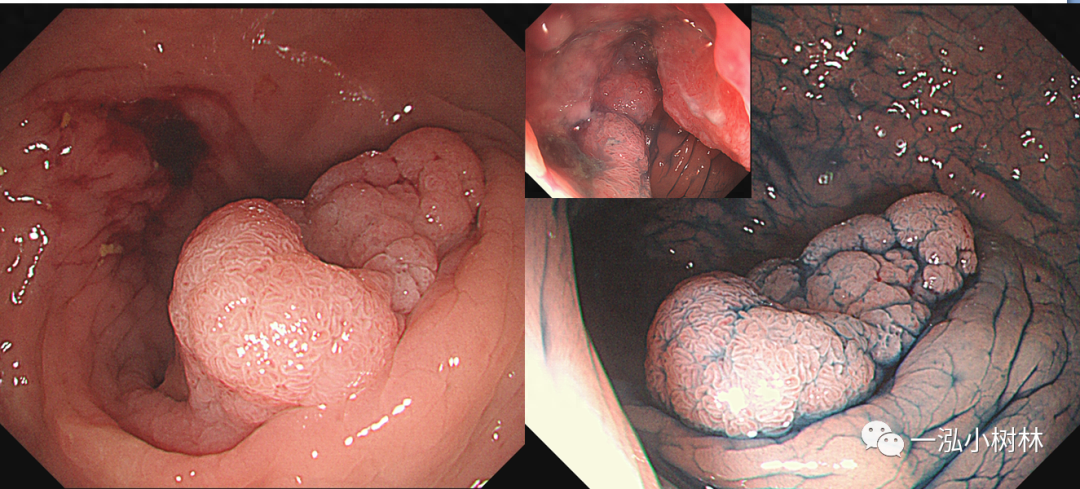

图1 结肠管状腺瘤(JNET2A型)

图2 结肠管状腺瘤(Pit Pattern IIIL型)